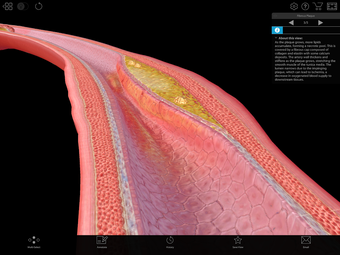

One of the most remarkable features of this application is that it enables users to compare 3D models of normal anatomy with models of common diseases and conditions. Furthermore, users can set the heart rate and visualize conduction in a dissectable, beating 3D heart while following along on an ECG. The application also presents animations that demonstrate the physiological processes of gas exchange, pulmonary ventilation, fluid balance, peristalsis, and more. Interactive lessons walk users through the progression of atherosclerosis, kidney stones, lung cancer, and other common conditions, and quizzes test users' knowledge of various physiological processes and pathologies.